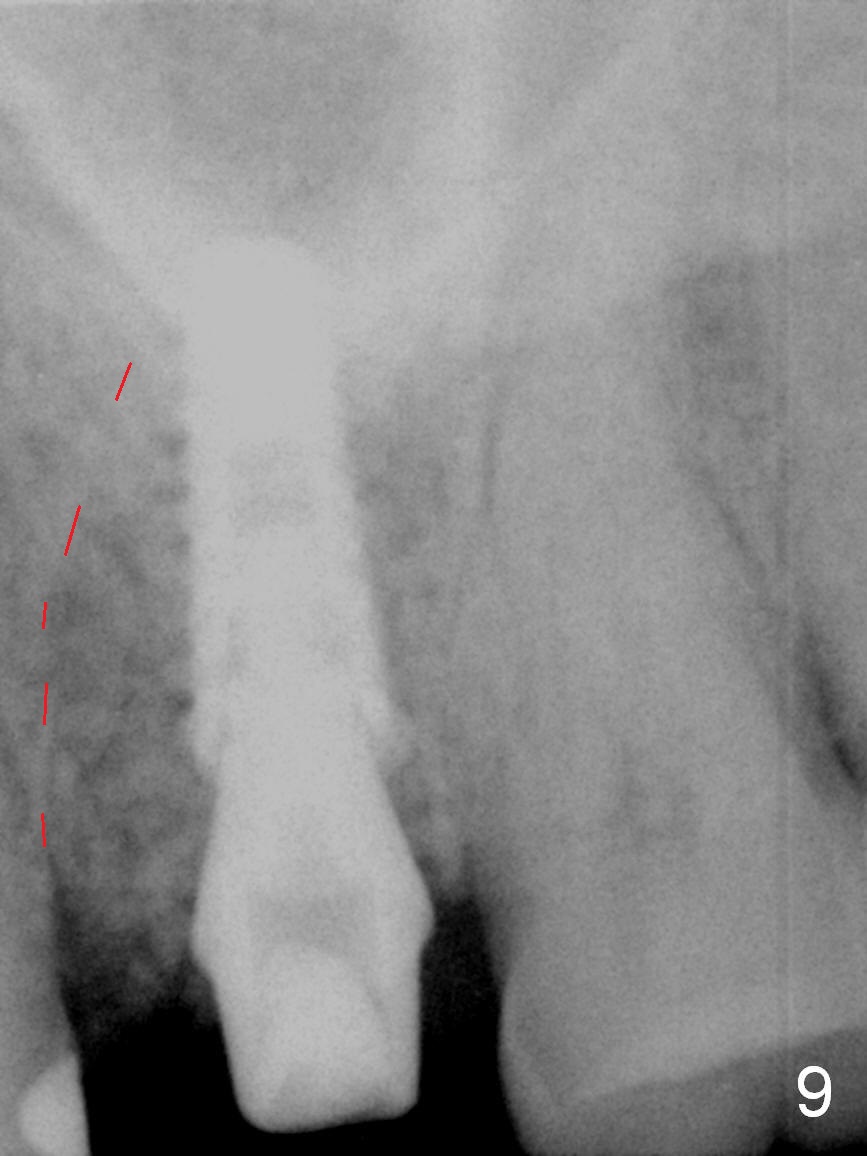

The septal bone is dense and the osteotomy is enlarged by alternating use of drills and expanders. By the time 3.8 mm ME is tapped in (Fig.6), the buccal plate of the septum is perforated. The ME is stable, in spite of the fact that it is only supported by 2-3 mm bone buccally (Fig.7). Continuously alternating use of MEs and drills leads to placement of a 5x11 mm implant with 30 Ncm insertion torque and sinus lift. After placement of bone graft (Fig.8 *) and 5x4(3) mm pair abutment (A), an immediate provisional is fabricated. Red dashed lines in Fig.6,9 represent the mesial outline of the socket, whereas black dashed in Fig.6 sinus floor. It suggests that the implant is stabilized by relatively small amount of native bone. Although IBS implants have aggressive thread patterns, a proper apical osteotomy should be prepared in the depth (perforates the sinus floor in this case) and diameter (4.3 mm drill) prior to placement.

It seems that the provisional traps food. The former has been removed by the patient by the time she returns 3.5 months postop. The gingiva around the implant is healthy. The organization of the bone graft has changed (Fig.13, as compared to Fig.8,9). The implant has osteointegrated. Take photos to show the buccal and palatal gingival margin before impression. In fact the newly formed gingiva covers the margin of the abutment 5 months postop (Fig.14). Laser gingivectomy is performed prior to impression. Provisional should be kept in place with good oral hygiene. The crown dislodges 8 months post cementation, probably due to bruxism, small, short abutment and open margin (Fig.15 (taken after recementation; the residual cement is removed later)).